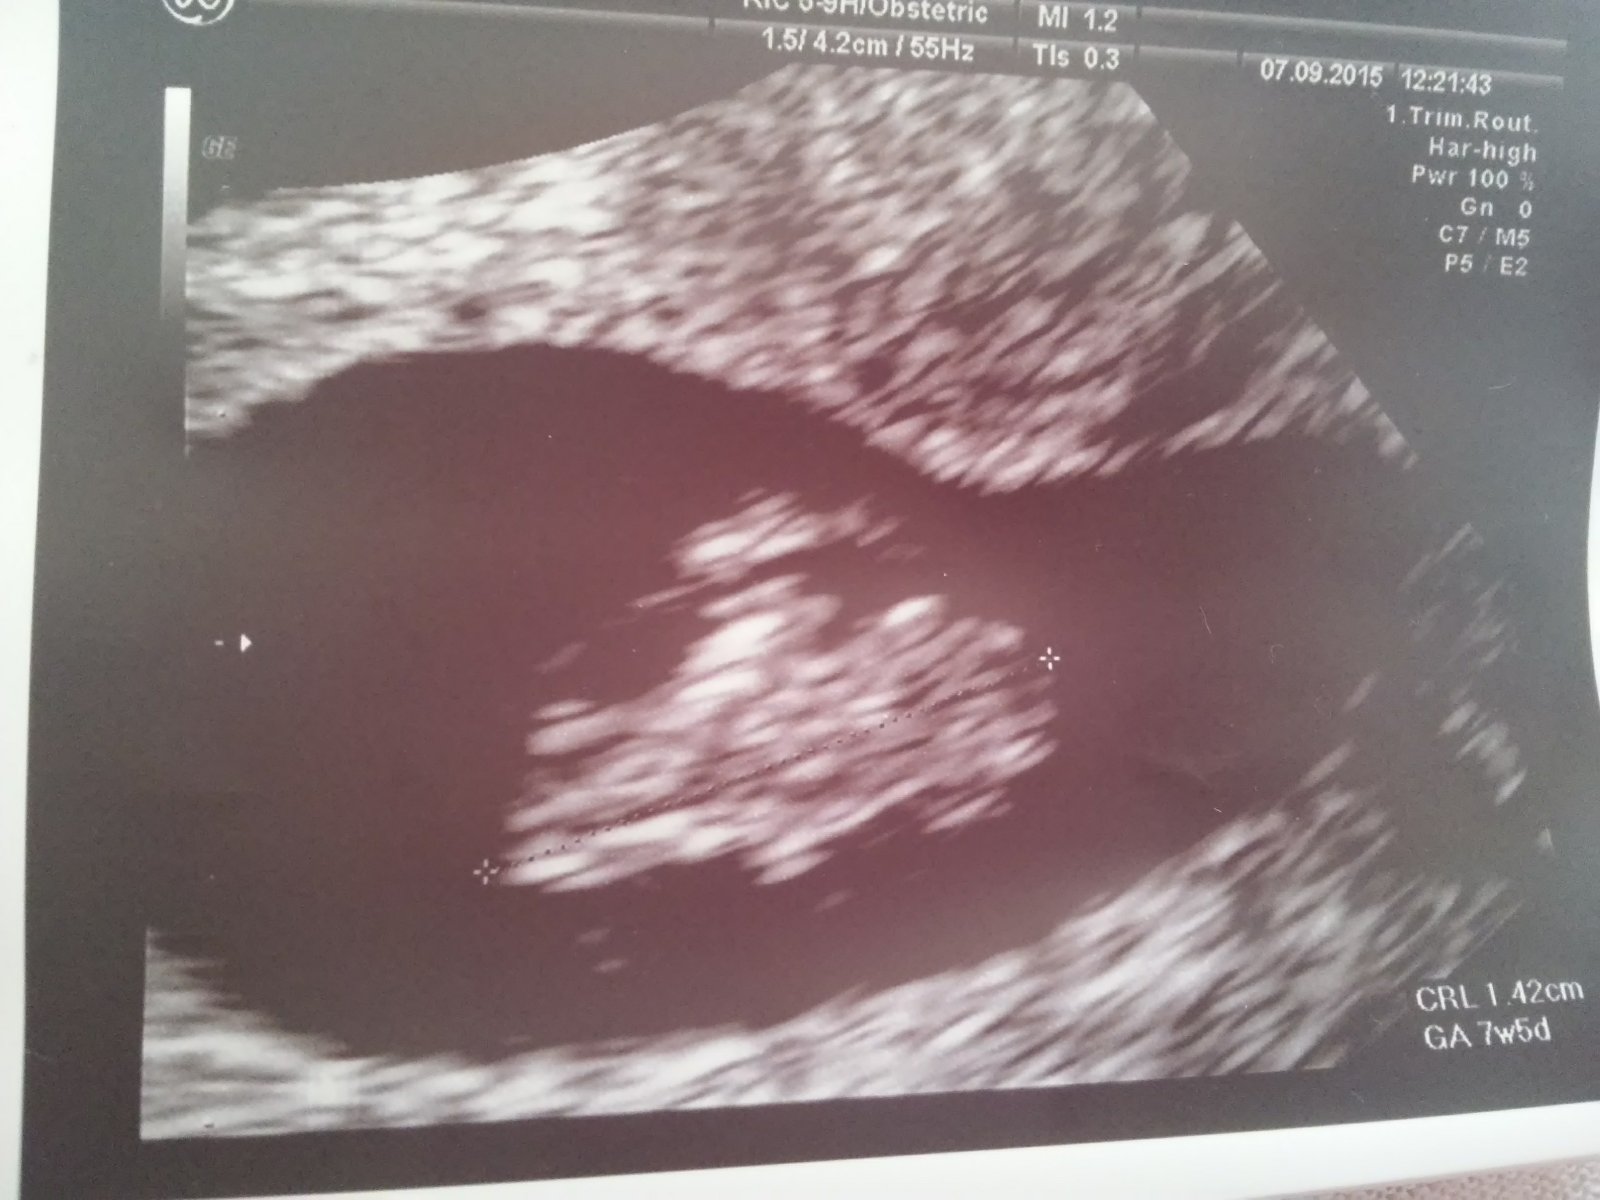

nam už v 6-7 tt tak na prelome bilo srdiečko

dievčatá , od stredy som slabo krvácala , veľmi som sa zľakla , v nemocnici skontrolovali bábo , srdiečko bilo pekne , dostala som injekciu a doktor mi predpísal vaginálne tabletky , teraz už je dobre.Podla sona som 6+6tt.

dnes som bola u toho doktora a vobec som nedostala dobre spavy,povedal ze je strasne maly a vobec mu zatial nebije srdiecko a to som 6t 5d prosim vas mala niektora zvas rovnaku situaciu ak ano ako to nakoniec dopadlo.som z toho strasne nestastna.povedal ze nech pridem za dva tyzdne a ked stale nic tak bude koniec,ja ani nevidim cez slzy co to tu pisem

@fiona2 je to u kazdej individualne...presne aj v 8tt sa niekedy rozbuchalo....

baby poradte. neviem kedy mam ist k doktorovi prvy krat som bola ked potvrdil tehu.a teraz mam ist na srdiecko som 6tt myslite ze uz bude vidno alebo mam este pockat?